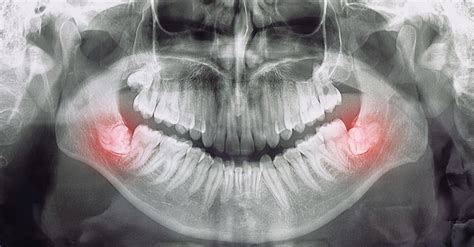

Un diente retenido se refiere a un diente que ha completado su desarrollo, pero no ha logrado emerger completamente de la encía ni tomar su posición normal en la arcada dentaria.

Definición: se refiere a un diente que no ha emergido completamente en la arcada dentaria.Características: Puede tener parte de la corona visible.

Mientras que el diente impactado se encuentra total o parcialmente dentro del hueso, el diente retenido ha completado su desarrollo, pero no ha emergido adecuadamente, y el diente incluido no ha erupcionado por completo, aunque no está completamente enterrado.